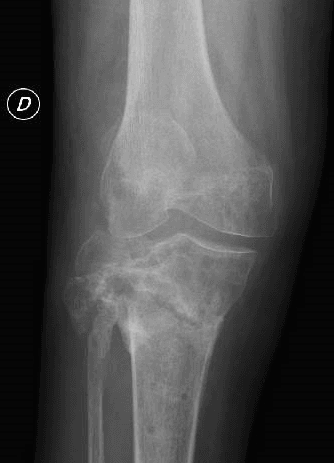

• Stadio IV: Formazione aggressiva di panno sinoviale con infiltrazione ed eventuale compromissione della cartilagine; radiologicamente evidenza di osteolisi subcondrale; formazione di erosioni ossee e cisti.

Se non diagnosticata e trattata tempestivamente, l’artrite settica può provocare danni permanenti alle superfici articolari, con rapida distruzione della cartilagine e compromissione dell’osso subcondrale, manifestandosi clinicamente con gravi limitazioni funzionali.